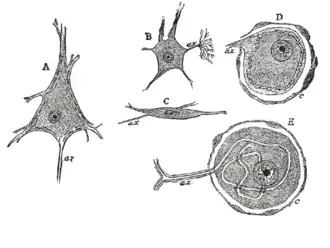

Various forms of nerve cells.

During the late 1800s, early 1900s, Spanish Neuroscientist and Pathologist Santiago Ramón y Cajal proposed Neuron theory which basically introduced the idea that the Nervous system contained cells called the Neuron. The process he used was called Golgi staining of the vertebrate retina. Cajal was able to differentiate between different types of Ganglion cell based on dendritic morphology, cell body and dendritic tree size, and number of sub layers in which they arborize/stratification layers. Through this study, he discovered that the ganglion cell distribution amongst vertebrates were pretty similar minus the Rods and cones in the retinas.[3]

In the 1940s, American Neurologist Stephen Polyak[4] produced description of the Golgi-impregnated Cells that helped further classify types of Ganglion Cells. This data helped scientists get a better understanding of the ganglion cells present in the retinas of Mammals and Primates[3]

In 1974, Boycott and Wassle created a scheme for the classification of Ganglion Cells that was found to be in the cat retina. These cells, alpha, beta, delta and gamma are seen to be linked with the X,Y and W types of physiology. Boycott and Wassle confirmed the idea of Cajal's Ox and Dog retina idea by naming the alpha and beta.